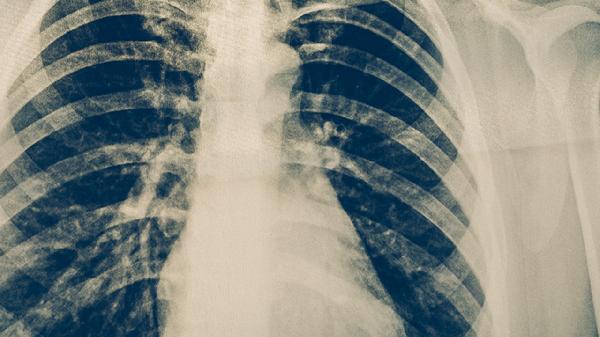

临床诊断需结合症状、影像学检查和实验室检测。血清学检查IgM抗体阳性有诊断价值,核酸检测灵敏度高但需专业设备。胸部X线多显示单侧斑片状浸润影,与细菌性肺炎的实变影有所区别。血常规检查白细胞计数通常正常或轻度升高。